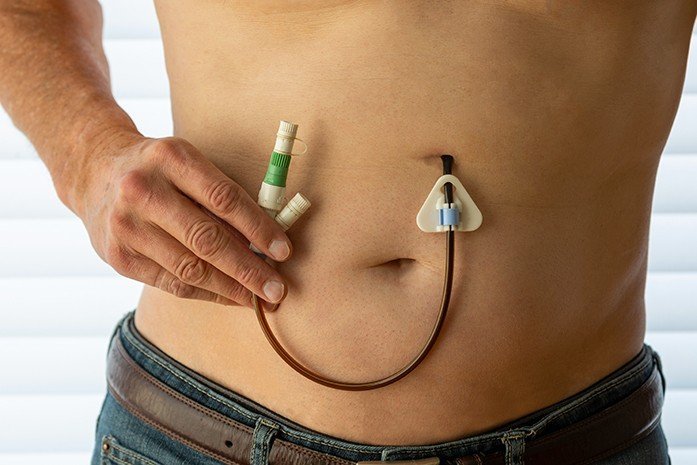

A specialized procedure used to diagnose and treat disorders of the bile ducts and pancreas. Common indications include: